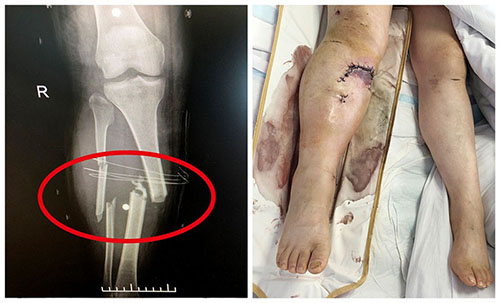

▲遭遇車禍的患者全身多處嚴(yán)重骨折